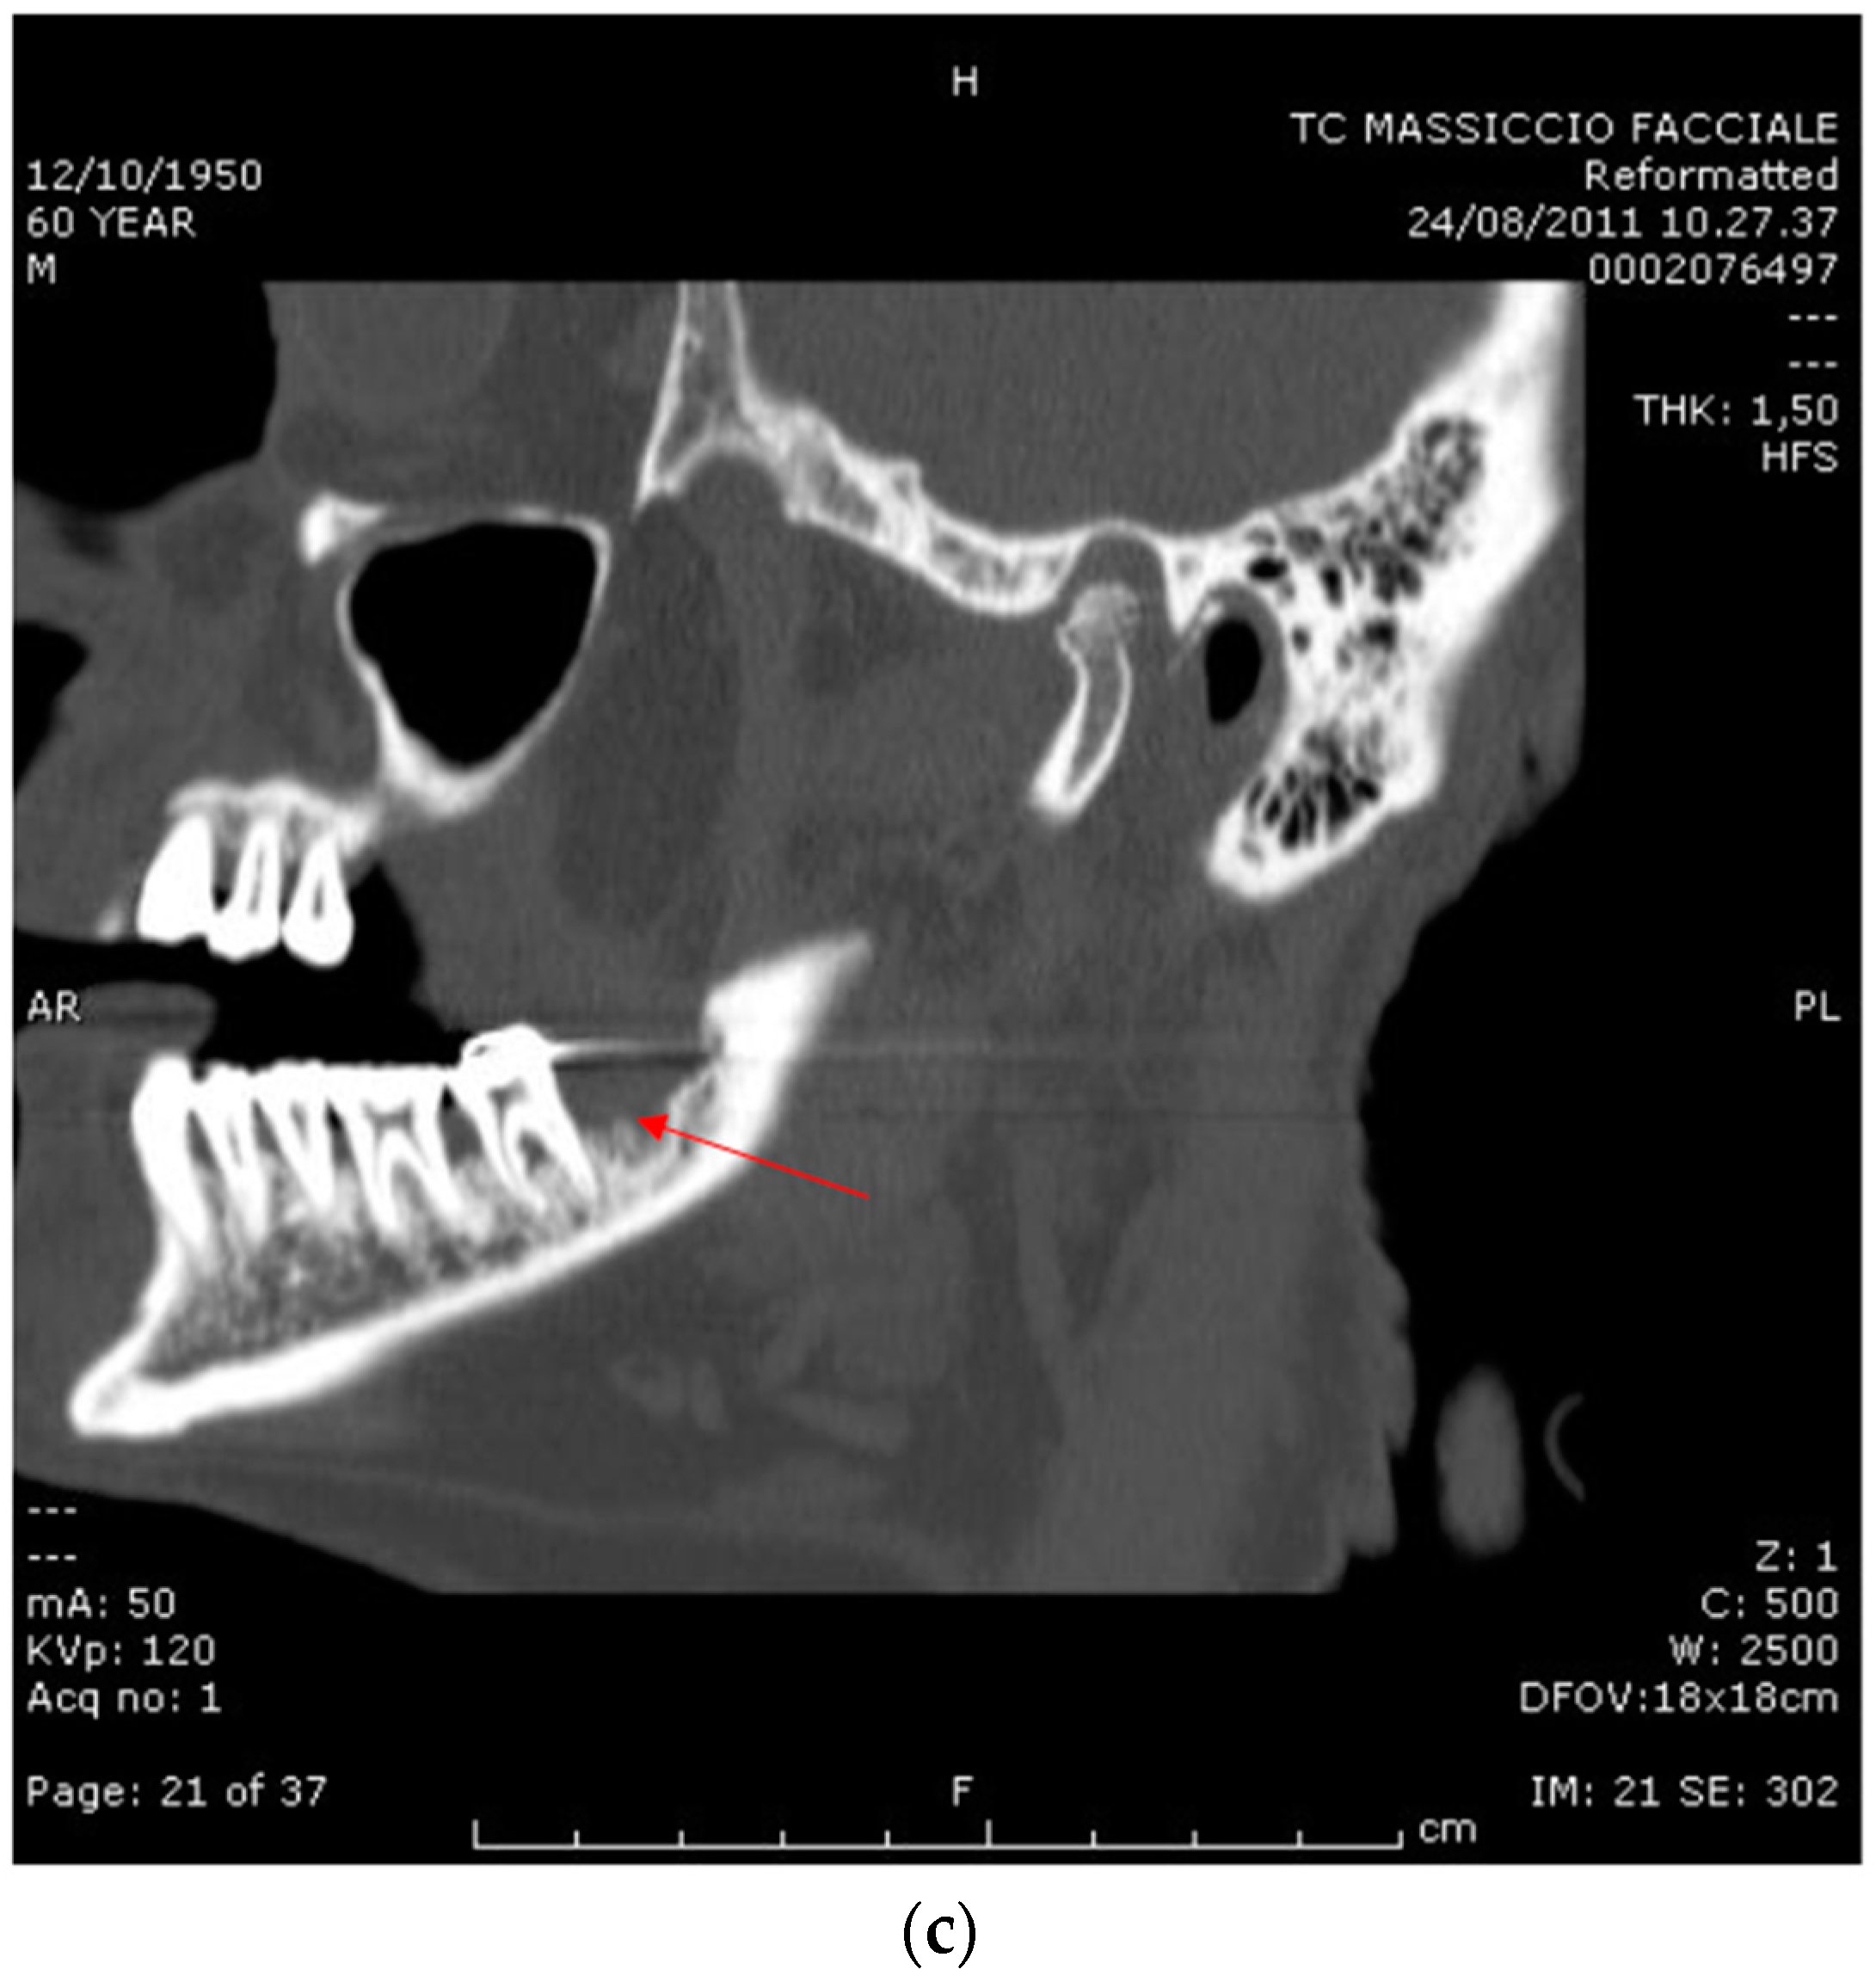

2.1. Case Report 1

2.2. Case Report 2